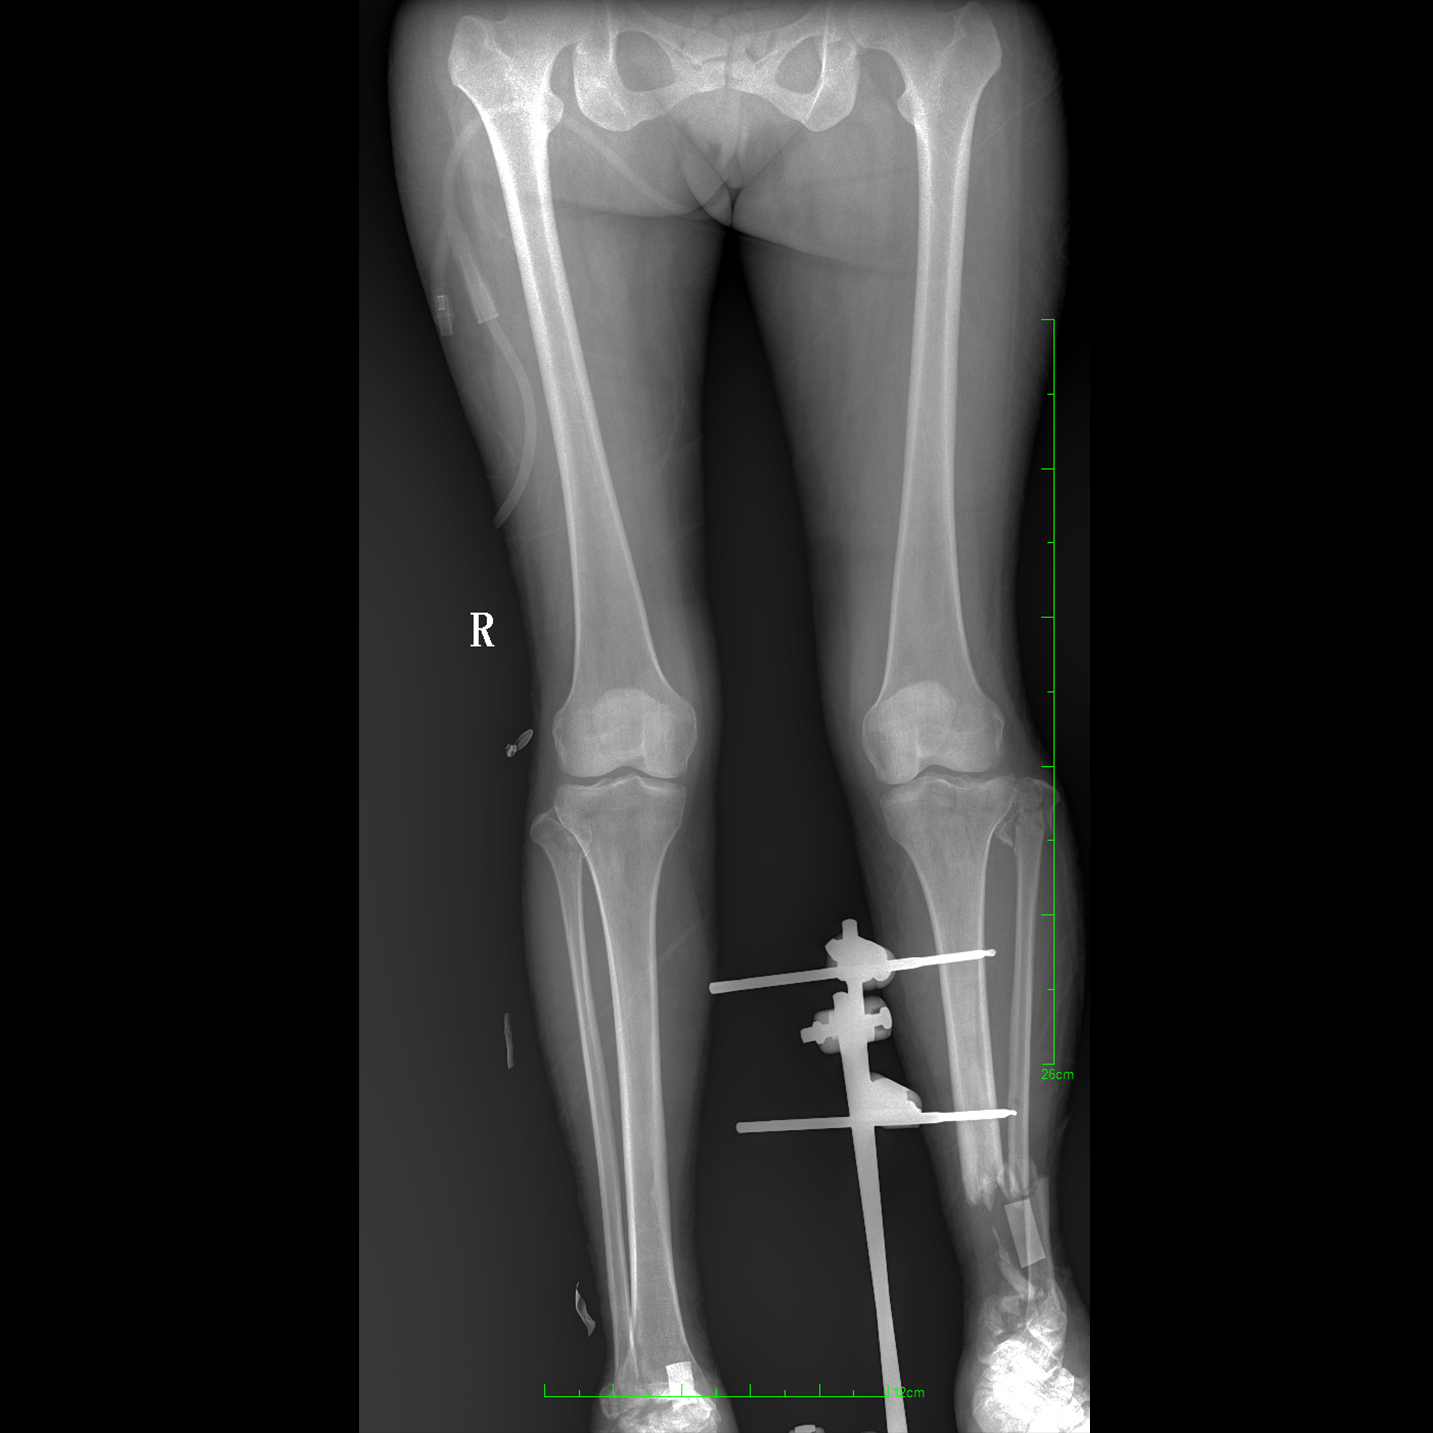

17"*34"有效視野,一次成像不拼接。相較于多張攝影再軟件拼接的DR設備,PLX8600解決了拼接圖像存在密度不均勻,拼接處圖像配準和放大效應等問題,給臨床帶來了大視野影像解決方案,可一次性覆蓋全脊柱或雙下肢影像。

除常規靜態攝影外,PLX8600大平板具備動態透視和點片功能,透視采集功能可支持大視野、多角度的可視化觀察。通過可視化的動態影像,配合點片功能,能夠很好的觀察復雜部位病灶,有效的抓取關鍵幀,降低患者多次攝片的概率。如:全脊柱狀態評估、長骨關節活動度、下肢靜脈造影瓣膜功能評估、消化道功能評估、脊髓造影等更多大視野臨床應用。